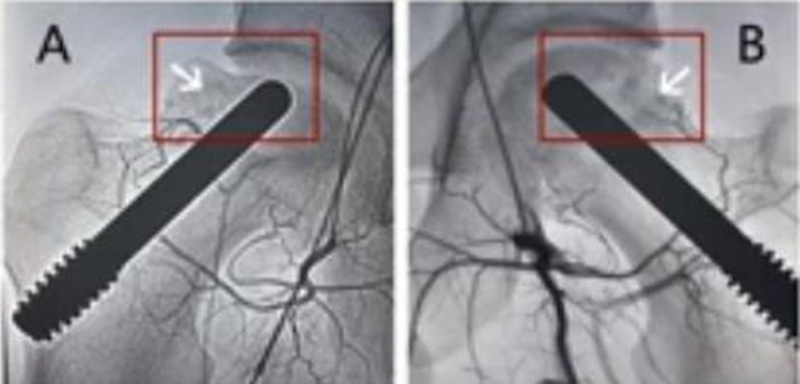

因髓芯减压联合非血管化骨移植术仍有待进一步研究,有学者就提出了髓芯减压联合血管化骨移植。血管化的移植骨块主要源于腓骨或者髂嵴,由于保留了血管,因此有助于改善坏死区的血运,促进坏死区域骨组织的修复重建。

Urbaniak等人报告了103例,血管化胖骨移植治疗股骨头坏死,Ⅱ期患者五年存活率为91%,Ⅲ期患者五年存活率为77%。Eward和Yoo等人的研究,血管化腓骨移植治疗股骨头坏死,Ⅱ期存活率为89%(平均随访13.9年)和Ⅲ期存活率为75%(平均随访14.4年)。Plakseychuk等人的进一步研究,回顾性地比较了血管化胖骨移植术与非血管化腓骨移植术,发现血管化腓骨移植队列的临床结局有更好的改善。笔者认为,血管化的骨移植将是今后发展的一个方向。

5、髓芯减压联合钽棒植入术

此方法最早由Pedersen提出,直到2005年多孔棒材料才广泛运用到临床研究中,浙江省中医院团队于2009年报告棒植入治疗早期股骨头坏死。一项138髋采取钽棒治疗,平均4年随访时间发现43例(31%)需再次实行髋关节置换术。Tsao在一项长达4年的研究中发现,19个关节(113)进行了再次的THA手术。Floerkemeier报道,在手术平均1.45年后,13例(23)需要再次THA手术,其结论是髓芯减压联合钽棒植入疗效不比单纯髓芯减压好。